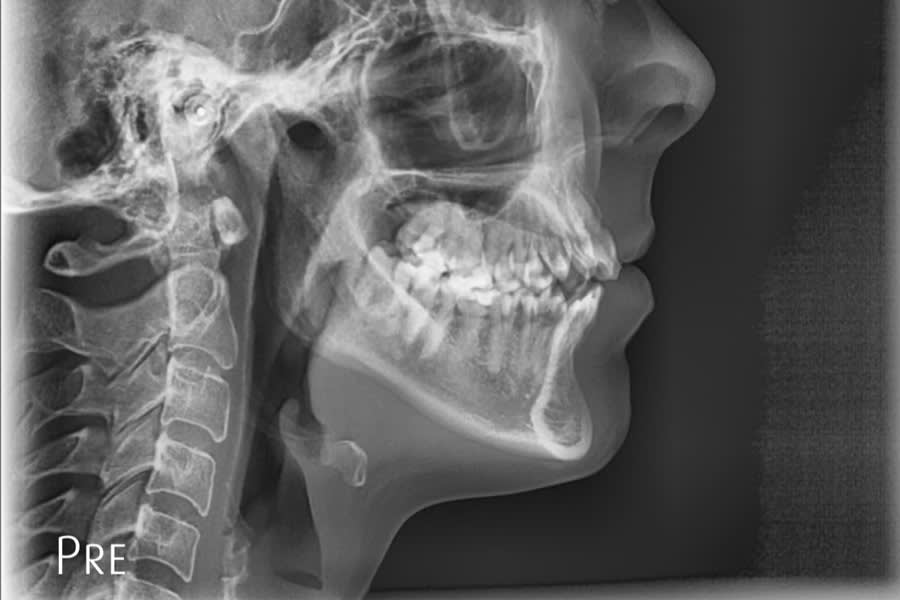

Radiographic Follow-up

Panoramic/cephalometric re-evaluation is used to document posterior intrusion without root resorption or sinus compromise, improved upper incisor angulation in bone, lip profile changes consistent with CCW autorotation, and favorable skeletal parameters.7,17-21 (Figure 18 through Figure 21)